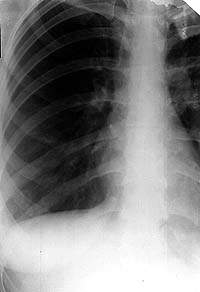

Фотографии, демонстрирующие обнаруженное усиление легочного рисунка

Раздел: Фотодневник открытий